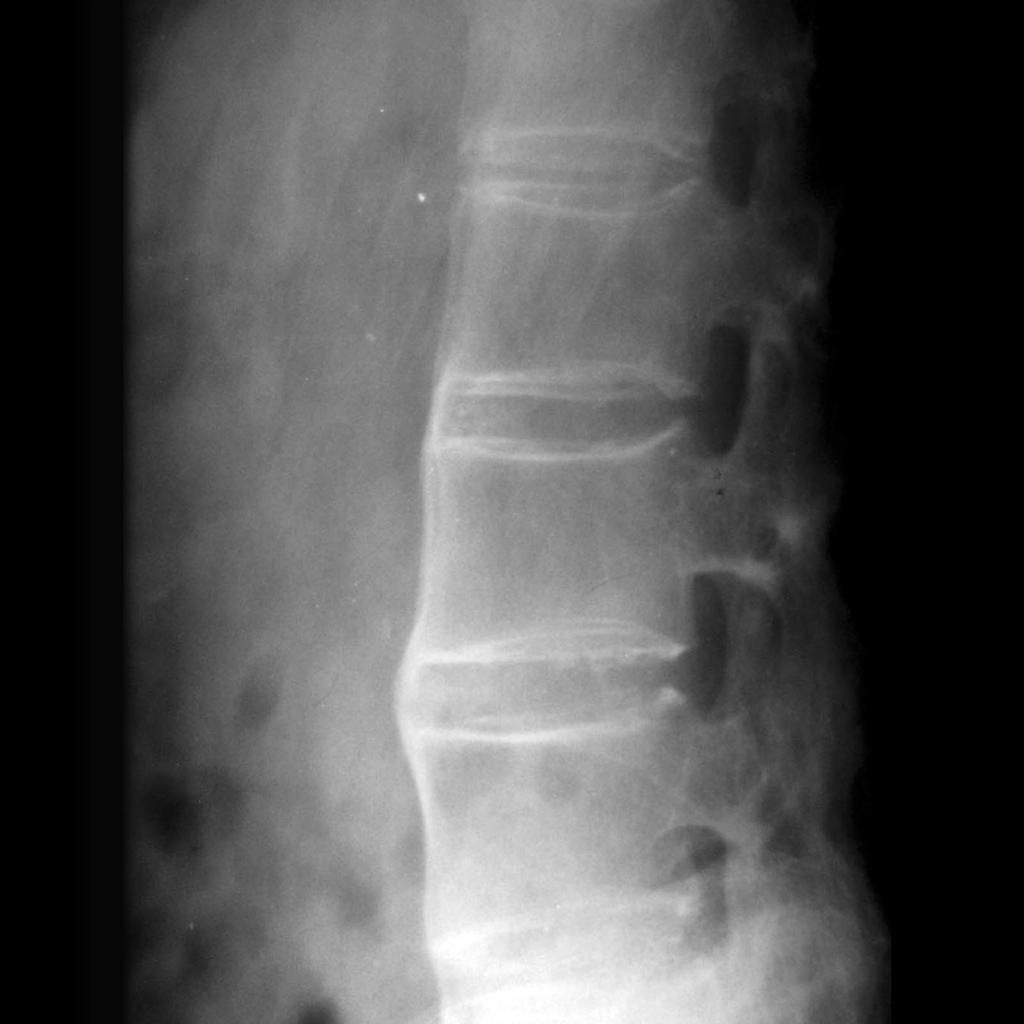

X线下的竹节样改变(并非所有人均如此,也并非所有人均会发展至此)